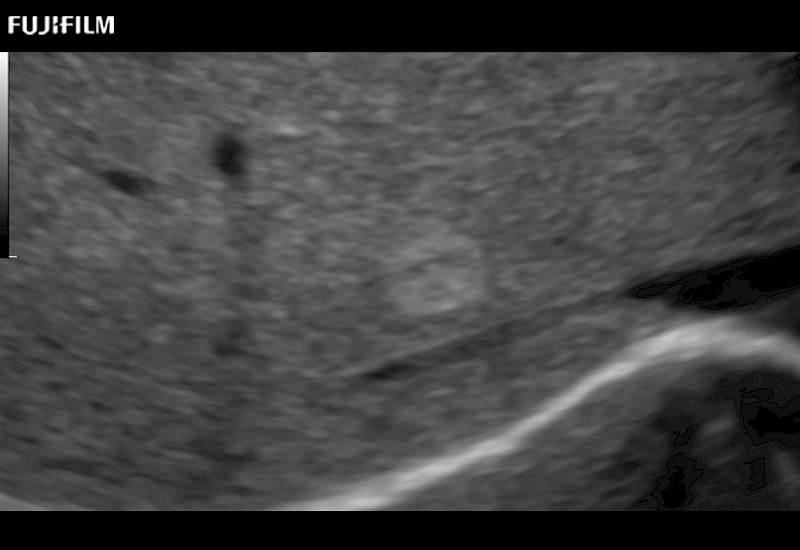

Extraordinary high-resolution digital imaging

- Exceptional near and far-field resolution

- Instant feedback on tumor margin delineation

- Valuable information to guide tumor resections

- Exceptional near and far-field resolution

- Instant feedback on tumor margin delineation

- Exceptional near and far-field resolution

- Instant feedback on tumor margin delineation